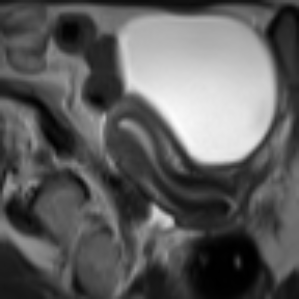

Image Reconstruction and Generation. Fig. 3 (left): Using LPIPS (AlexNet), the AE trained on FUNDUS achieved a score of on both full volumes and central slices (Z0), while the VAE reached . Applying ROI cropping to FUNDUS increased LPIPS to for the AE and for the VAE. All UMD inputs were evaluated without cropping to ROI. We evaluated 2D and 3D DDPMs using FID and LPIPS across uterine orientation classes and conditioning setups (Tab. 1): class only, class + ROI, class + text (C+T), and C+T + ROI. Example images for qualitative evaluation are shown in Fig. 2. All 2D models were trained on the central slices for evaluation, trained on all slices in the volume, FID and LPIPS increased by at minimum. Text-conditioned models without class-conditioning performed worse than class-only conditioned models in an extended ablation study. The 2D DDPM with C+T + ROI conditioning consistently achieved the best results. ROI cropping alone also improved performance, especially when combined with semantic input. In 3D, the best results came from class + ROI, though overall quality lagged behind 2D models. In Tab. 2, the ablation study shows that conditioning with class and text information combined with ROI preprocessing consistently improves image quality across DDPM and LDM models, with 2D LDMs achieving the best overall FID and LP scores.

Synthetic Datasets. The SynthUterus datasets include scans with synthetic images per class for each uterine position and are balanced to match the FUNDUS dataset distribution (Fig. 1). Two versions were generated using class and text conditioned DDPMs: full images referred to as SynthUterus and uterus-focused region of interest crops referred to as SynthUterus ROI, capturing semantic and spatial details to improve training. Ten real and ten synthetic healthy pelvic ROI MRI samples were classified by three groups: non-expert AI researchers, less experienced radiologists and experienced pelvic radiologists. Their accuracies were , and respectively, showing limited ability to distinguish real from generated images.